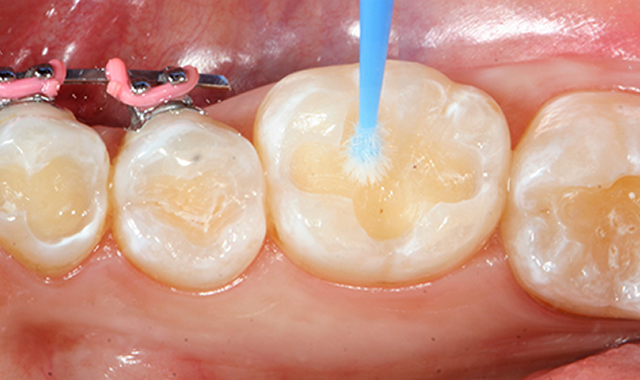

Some preps have enamel and dentin in equal amounts, while other preparations are all dentin. Some preps are so small and minimal that they’re all in enamel. Dr. Goodchild explains you should be flexible when it comes to etching teeth for a bond. In other words, whether you use a total-etch or a self-etch system depends on the size and shape of the prep.

“At the end of the day, we have to know that if we have enamel, we'd like to etch it, and when we have a lot of dentin, we’d like to be judicious with etching. So, having systems that allow for that is where we are now,” Dr. Goodchild says.

The next evolution of bonding systems looked for a middle ground, which is to say a bonding agent that could either have total-etch or self-etch. Dr. Goodchild explains with these types of “middle-ground” systems, you can also enjoy the benefits of etching enamel without worrying about a little getting on the dentin because it won’t cause a problem.

“We now understand that etching enamel when you can creates the best bond,” Dr. Goodchild says. “And keeping phosphoric acid off of dentin is probably a good idea. So, that's why we have to pick the right stuff for the right indication because some preparations have a nice mix of enamel and dentin."

“The ideal combinations of these two modes is selective-etch,” Dr. Lawson agrees. “In other words, employ phosphoric acid application on the enamel and self-etch application on the dentin."